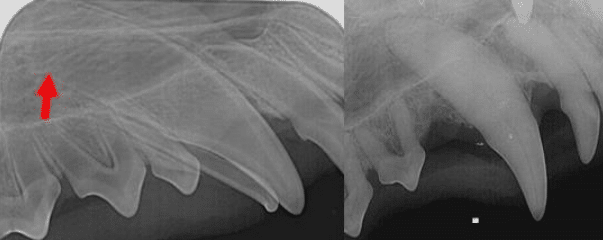

de loop der tijd steeds smaller wordt. Als er iets plaatsvindt waardoor het wortelkanaal afsterft (bijvoorbeeld bij een bloeding in de tand door stomp trauma) wordt de tand niet meer ouder en daarmee het wortelkanaal niet meer smaller. Dit is goed te zien op de gemaakte dentale foto, de rechter hoektand op de foto heeft een stuk breder wortelkanaal dan de linker.

Op onderstaande afbeeldingen is goed het verschil te zien tussen een jonge hoektand en een volwassen uitontwikkelde hoektand. Op de linker afbeelding bij de rode pijl is de nog niet gesloten wortelpunt te zien. Op de rechter afbeelding is een volwassen doorontwikkelde hoektand te zien.